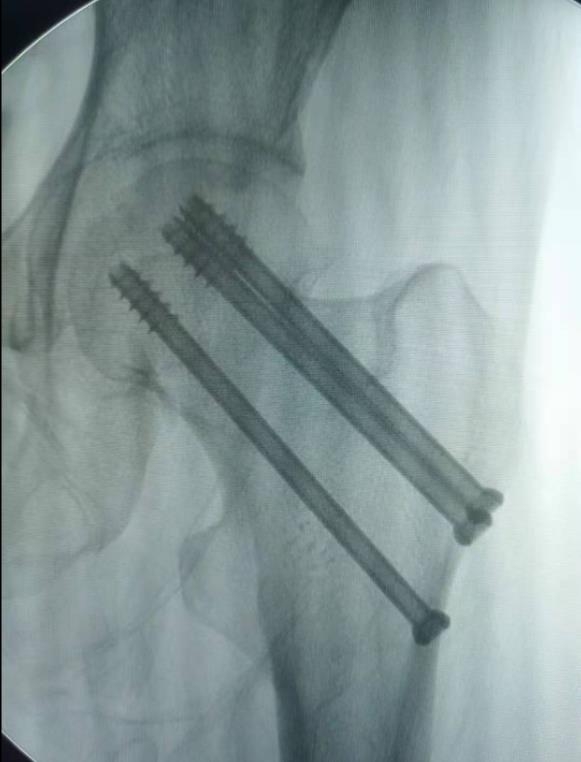

1、经皮沿股骨颈轴线置入空心钉导针,确保导针平行;

2、标准放置螺钉为倒三角形,其中下方螺钉在股骨矩,后方螺钉在后方骨皮质、研究发现倒三角形平行三枚螺钉能提供最佳的固定强度;

3、螺钉位于股骨颈四周,特别是后侧及下方,避免低于小转子方向进针,可能导致术后转子下骨折;

4、两个平面透视导针位置良好后切开皮肤,空心钻铭孔,导针引导下拧入空心钉,空心钉确保所有螺纹位于骨折线近端,螺钉头应距离软骨下骨5mm。

图2 倒品字固定